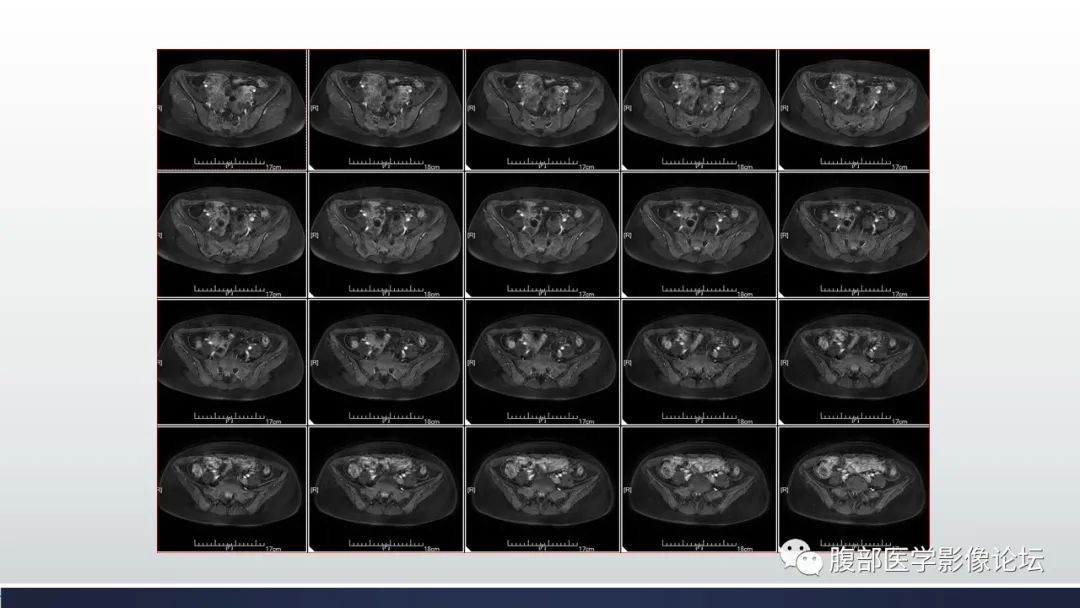

【病例】子宫内膜透明细胞癌1例MR-2